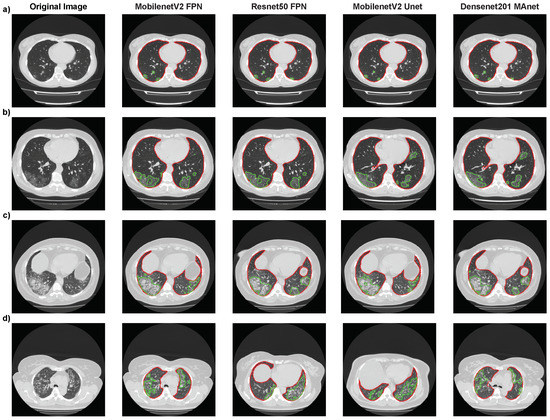

We first applied our architectures to the other 1010 full CT scans of MosMedData to validate our pipeline in a 3D scenario to detect and segment all lesions in an exam and then classify the exam as “with lesion”, if any lesion was found, or “without lesion”, otherwise. The results are summarized in Table 8.

All architectures had similar and competitive results on MosMedData. Mobilenet Unet had the highest accuracy, F1-score, and recall, with 94.36%, 96.5%, and 97.39%, respectively. However, it only achieved the specificity of 82.35%. Densenet201 MAnet obtained the highest precision and specificity, with 97.23% and 90.2%, respectively. However, it achieved lower accuracy, 87.82%, and recall, 87.22%.

These metrics indicate that Mobilenet Unet had the smallest number of false negatives (21 exams or 2.60%) but a higher number of false positives (36 exams or 17.65%). Therefore, as missing a positive exam over a negative is more critical, Mobilenet Unet might be an efficient option to detect COVID-19 on MosMedData.

Then, to evaluate our architectures’ robustness, we performed external validation on the SPGC dataset, which was not on the training/validation/test sets, thus having a different distribution from our original images. Furthermore, the SPGC dataset has CAP exams, which were added to the “with lesion” class. Table 9 presents the results of all architectures evaluated in this work.

All architectures had similar and competitive results in the external validation on the SPGC dataset. Mobilenet Unet had the highest accuracy and F1-score, with 98.05% and 98.7%, respectively. Thus, we answer RQ2, as Mobilenet Unet detected exams with COVID-19 and CAP lesions and exams without lesions.

By merging the segmentation, detection, and classification tasks, we obtained the confusion matrix in Figure 8. For lung segmentation, we applied Resnext101 Unet++; for lesion segmentation, we applied MobilenetV2 Unet; and for COVID-19 or CAP classification, we used Densenet201. These architectures were selected according to their overall results, mainly focusing on a low false-negative rate.

The confusion matrix shows that the classifier performed well in the COVID-19 class, with a high number of true positives (168) and a low number of false positives (3). However, there were some misclassifications, as 35% of CAP exams were classified as COVID-19. These results suggest that our classification models could not differentiate between the two classes or that there was insufficient information on the CT slice to differentiate between them.

Figure 8. Final results using MobilenetV2 Unet for lesion detection and Densenet201 for COVID-19 or CAP classification.